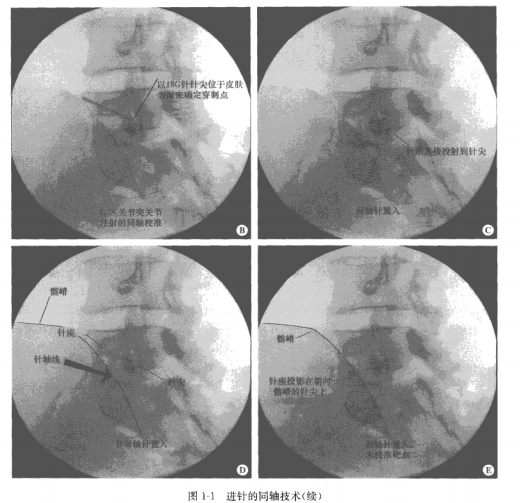

A.顯示同軸左側(cè)腰椎關(guān)節(jié)突關(guān)節(jié)內(nèi)注射的恩者體位和(C形臂的軸線圖像。針體的軸線在C圖(同軸)和D圖(偏離軸線)顯示。B經(jīng)調(diào)整后顯示L5/S1的關(guān)節(jié)突關(guān)節(jié)和關(guān)節(jié)面。一根18G的穿刺針經(jīng)表皮與靶點(diǎn)位置在影像學(xué)上重疊,決定進(jìn)針麻醉的皮膚位點(diǎn)。C經(jīng)同軸技術(shù)針體在l5/S1關(guān)節(jié)面上方顯示良好,針體在針尖正上方。D.抵至L5S1關(guān)節(jié)面的針與X線束不同軸,顯示側(cè)位和正中位。E經(jīng)過同軸調(diào)整后進(jìn)針,但是不能位于L5/S1關(guān)節(jié)面的靶點(diǎn)(×)上方

在圖1-1中顯示了腰椎小關(guān)節(jié)內(nèi)注射的同軸技術(shù)。通過C形臂的轉(zhuǎn)向X線顯示不同

的關(guān)節(jié)軸線(見圖1-1A),腰椎小關(guān)節(jié)的注射可以在清晰圖像引導(dǎo)下進(jìn)行。一旦小關(guān)節(jié)顯示清晰,應(yīng)用一根不透X線的穿刺針經(jīng)表皮直至抵達(dá)靶位關(guān)節(jié)(見圖1-1B)。應(yīng)用這種技術(shù),表皮至靶點(diǎn)的整個(gè)路徑在X線軸位

上均可顯示。表皮和皮下組織的麻醉藥也可以直接通過有標(biāo)記的針尖給予。穿刺針首先進(jìn)入一小段距離,當(dāng)皮下組織至靶點(diǎn)的路徑確定后再進(jìn)針口針的角度可以適當(dāng)調(diào)整,因?yàn)樗荒苁冀K與X線的方向完全平行。最初的調(diào)整可以不用影像學(xué)介導(dǎo)——需要估測C形臂射線的軸線方向,并調(diào)整最初穿刺針的軸向,有必要使它們大致處在同一軸線上。進(jìn)針首先要淺,當(dāng)與X線曝光軸線對齊后再繼續(xù)進(jìn)針(見圖1-1C)。當(dāng)針的針干和針尖重疊并可見到中心可透光的圓圈時(shí),就表明針與X線曝光軸完全對齊了。只有在穿刺針調(diào)整成這樣的位置時(shí)才可以繼續(xù)進(jìn)針。這里給出了一些最初固定針方向困難的例子:圖1-1D顯示針的方向不易調(diào)整,圖1-1E顯示針的軸向調(diào)整好了,但是沒有與靶點(diǎn)對齊。只要穿刺針的方向直對靶點(diǎn),就可以繼續(xù)進(jìn)針直至抵達(dá)靶點(diǎn)。如果穿刺針的軸線并沒有覆蓋靶點(diǎn),那么穿刺針需要調(diào)整位置并移動(dòng)直至覆蓋靶點(diǎn)。穿刺針方向和射線軸向小的偏差很容易糾正;大的偏差就不可避免地會(huì)導(dǎo)致針的路徑偏離最終靶點(diǎn)位置。